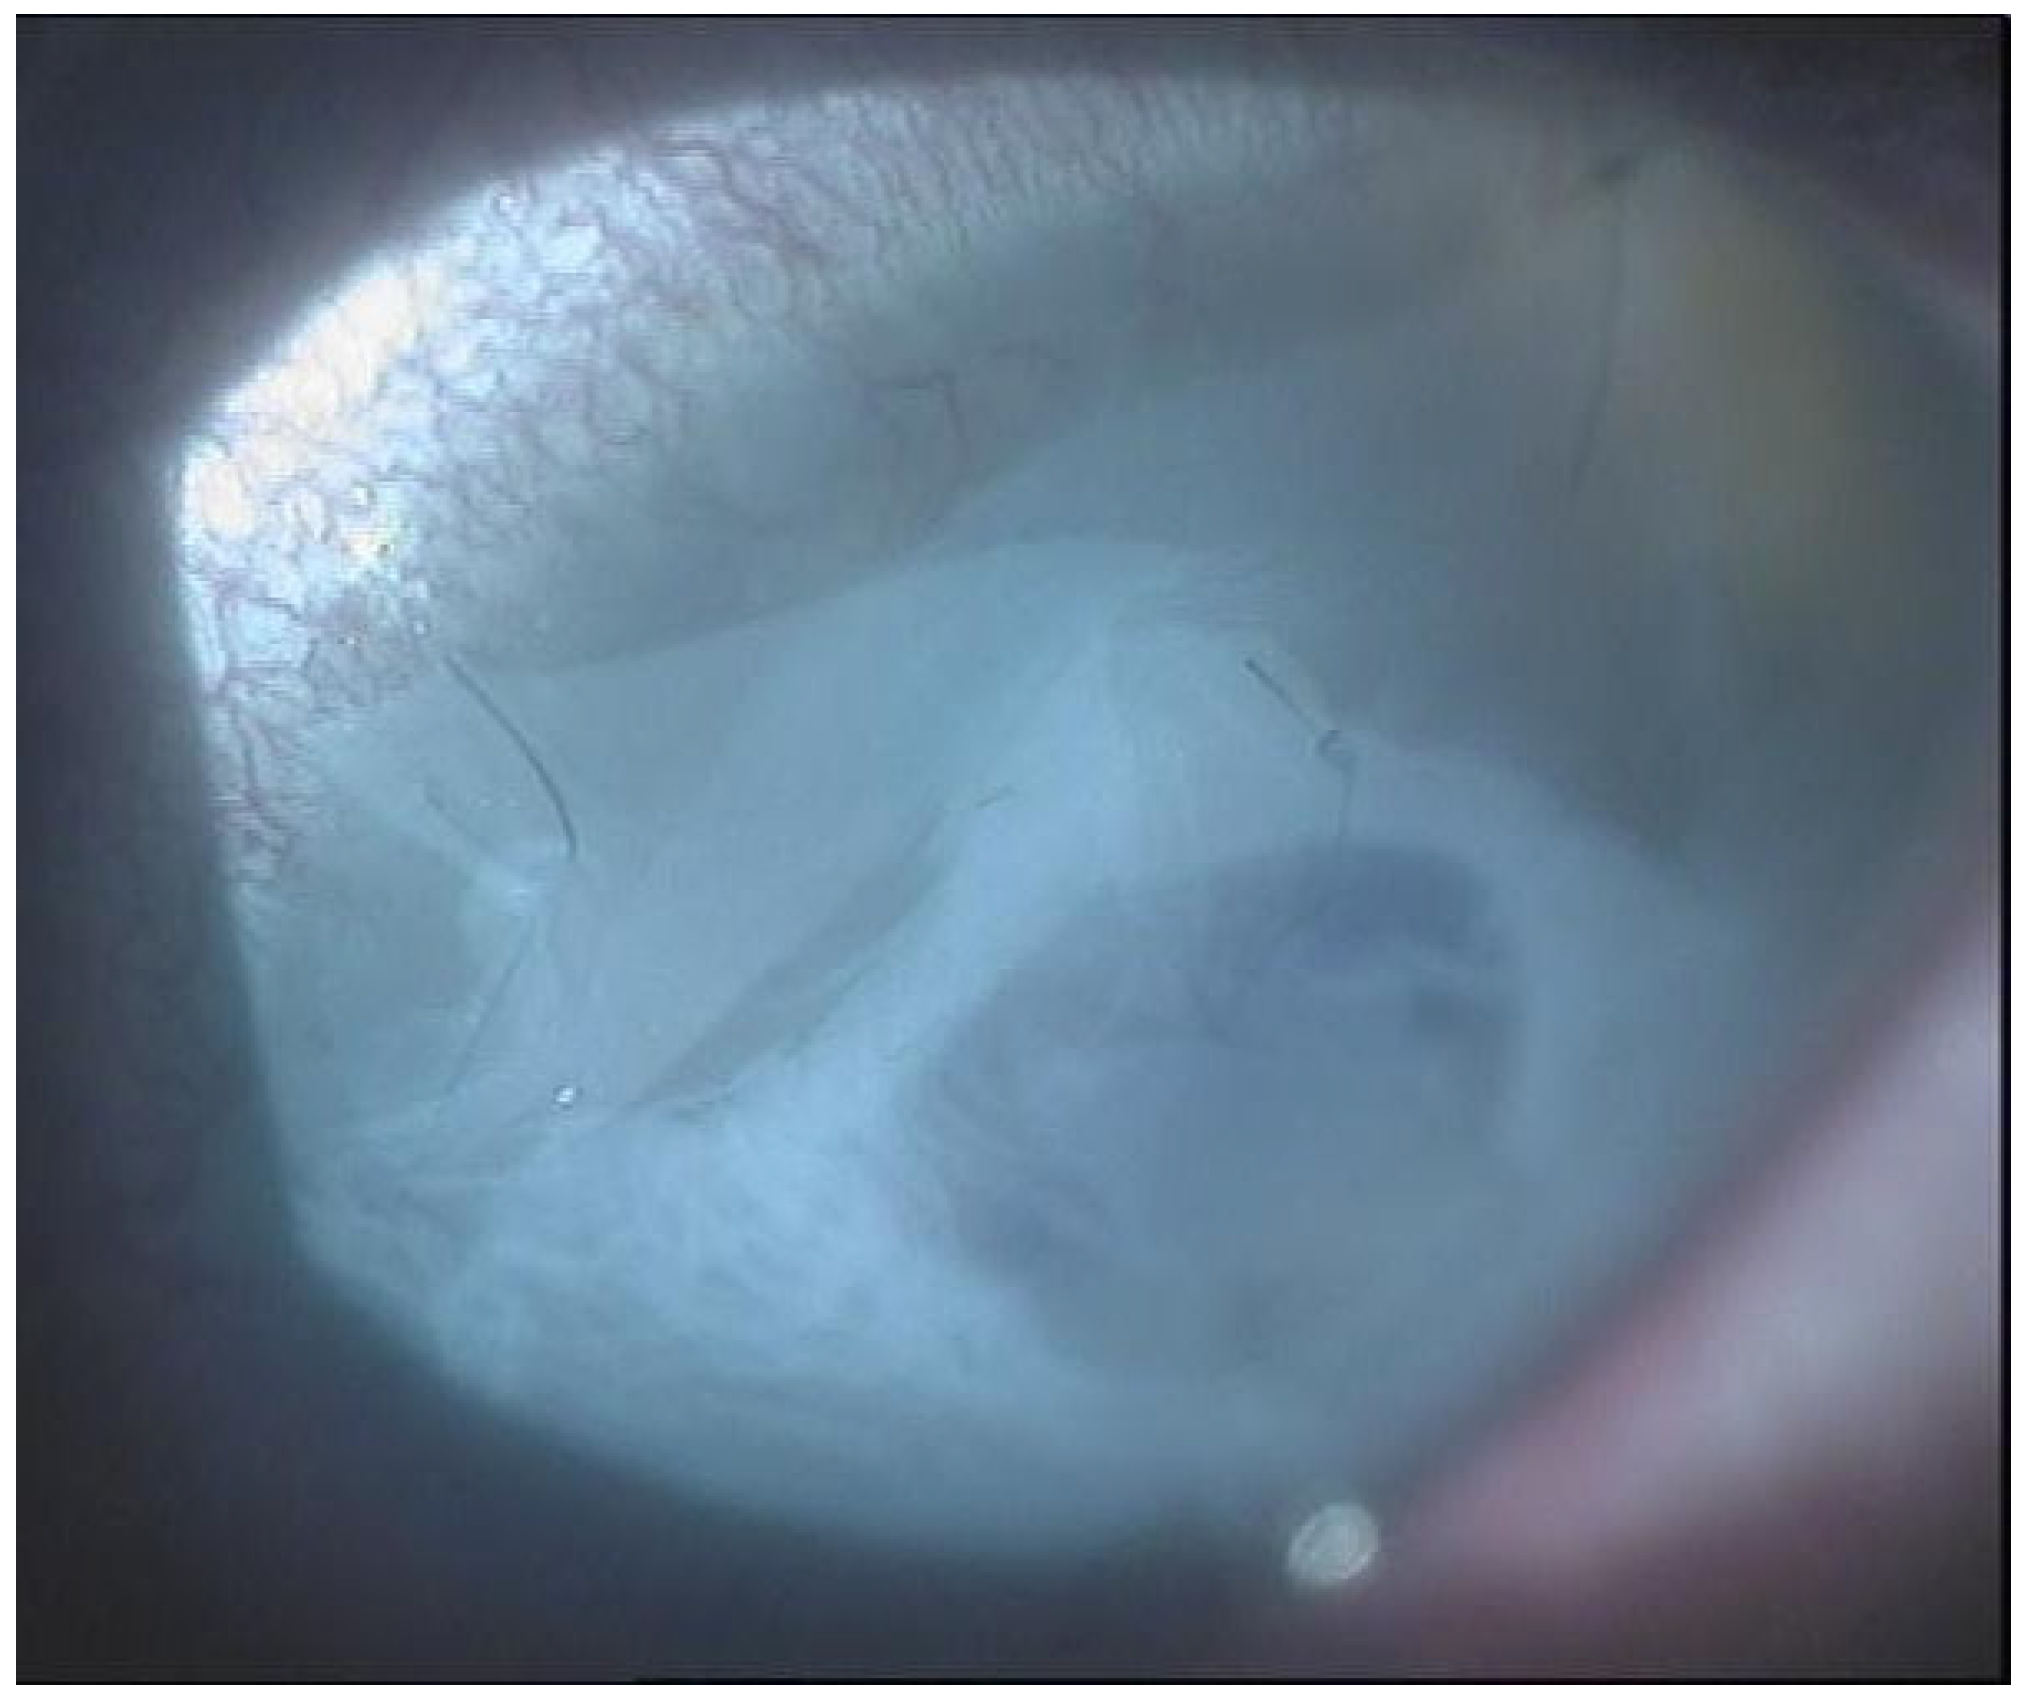

Figure 3. Anterior segment biomicroscopy of 8.25 mm diameter penetrating keratoplasty (PKP) with amniotic membrane overlay, 1 week after surgery.

Recurrent ulceration over the graft required a second patch procedure in March 2024. Subsequently, in April 2024, a full-thickness 8.25 mm PKP was performed. During penetrating keratoplasty, the donor lenticule (8.25 mm) was similarly wrapped using cryopreserved AM. The membrane was folded in a U-shaped configuration around the donor cornea, extending beyond the graft margins to cover the graft–host interface circumferentially. The same orientation was maintained (stromal side inward, epithelial side outward). The graft was then sutured to the recipient cornea with interrupted 10-0 nylon sutures, anchoring both the donor tissue and the AM envelope simultaneously. (Figure 3, Figure 4 and Figure 5).